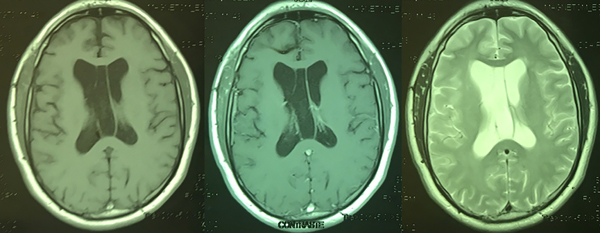

Se realizó la exéresis macroscópicamente completa de la lesión a través de una craneotomía y ulterior corticotomía a nivel del giro frontal medio derecho, colocándose finalmente una derivación ventricular externa (Figura 2). La anatomía patológica reveló una histología compatible con subependimoma grado I de la OMS (Figura 3). El paciente permaneció internado por 3 días en la unidad de terapia intensiva, pasando luego a piso donde se retiró la derivación ventricular externa y fue dado de alta hospitalaria al 5to día post operatorio sin complicaciones. Se realizó una RM control la cual evidenció la resección macroscópicamente completa de la lesión (Figura 4).

Figura 4: Resonancia magnética que evidencia la exéresis completa de la lesión.